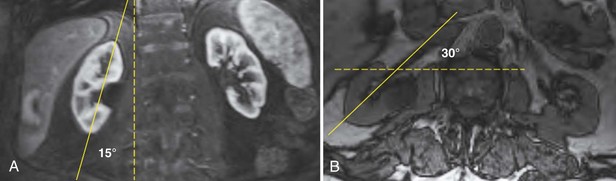

It is helpful during scanning of the kidney to understand its anatomic position within the retroperitoneum. This assists identifying the midsagittal plane, which serves as a reference point for a complete examination (Fig. 4–31).

Figure 4–31 The lower pole of the kidney is displaced 15 degrees laterally compared with the upper pole (A). The kidney is rotated 30 degrees posterior to the true coronal plane (B). The lower pole of the kidney is slightly anterior compared with the upper pole.